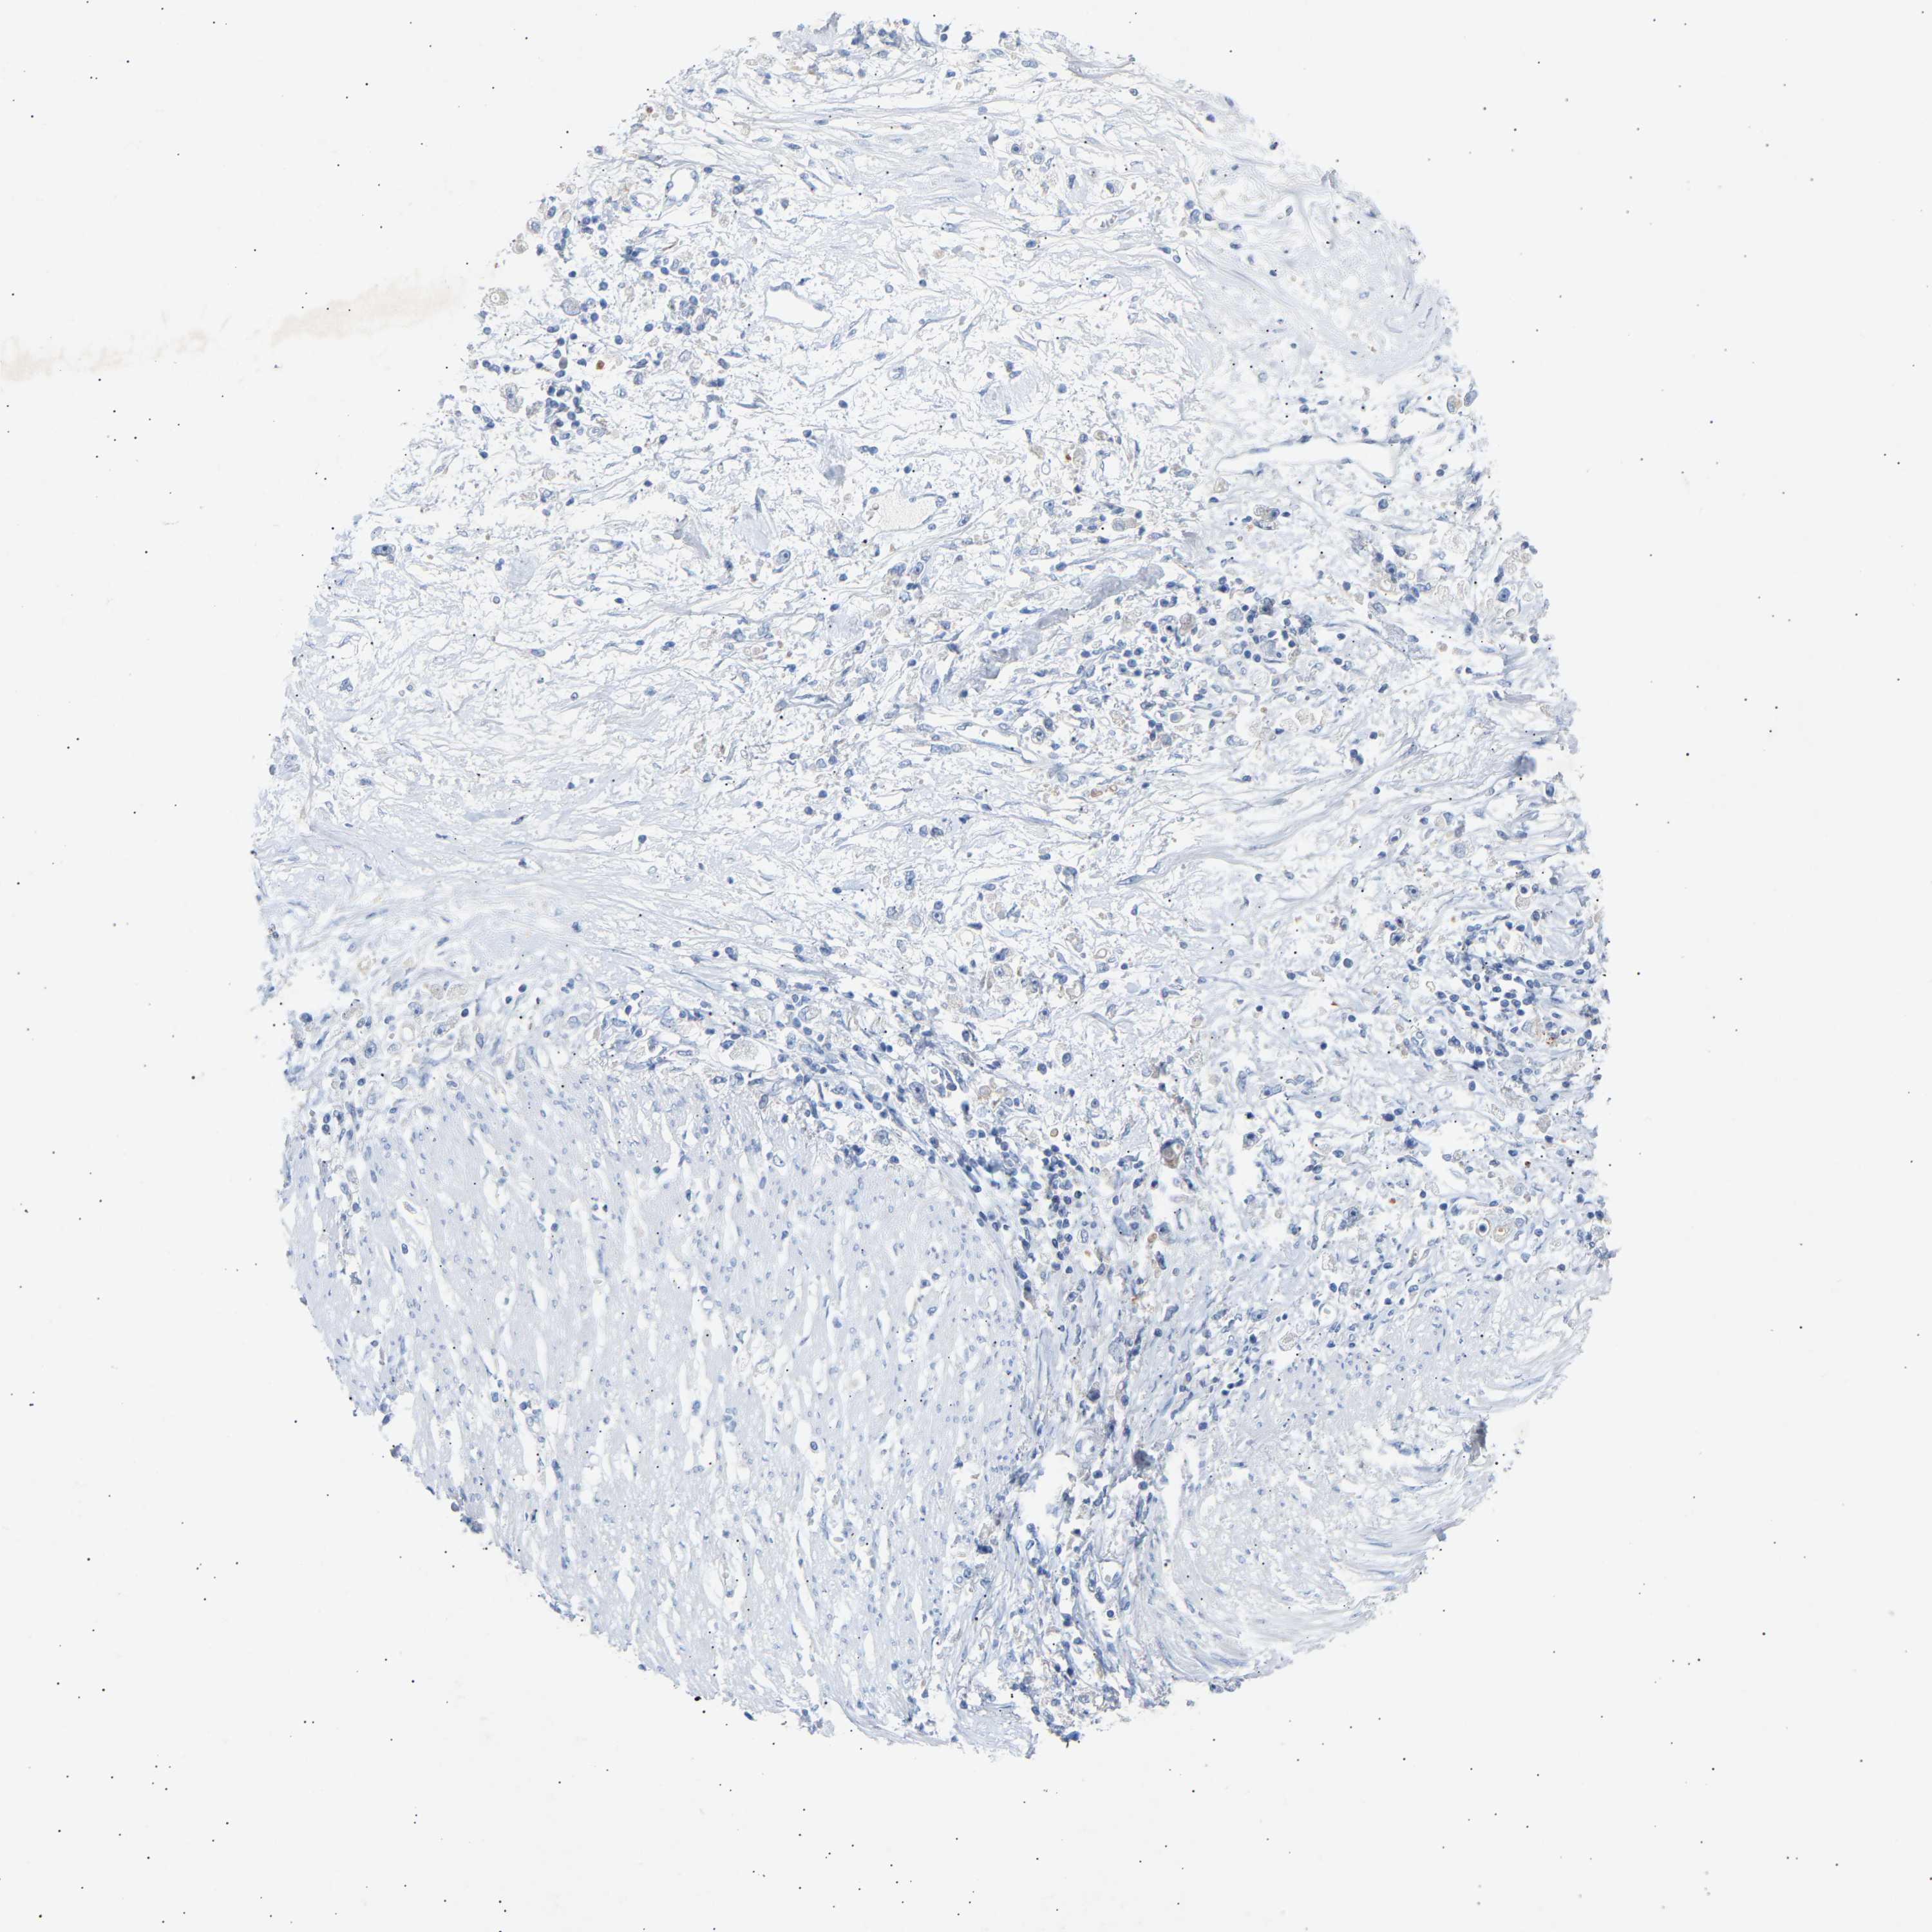

STOMACH CANCER - Protein expressioni

A mouse-over function shows sample information and annotation data. Click on an image to view it in a full screen mode. Samples can be filtered based on level of antibody staining by selecting one or several of the following categories: high, medium, low and not detected. The assay and annotation is described here.

Antibody stainingi

Antibody staining in the annotated cell types in the current human tissue is reported as not detected, low, medium, or high, based on conventional immunohistochemistry profiling in selected tissues. This score is based on the combination of the staining intensity and fraction of stained cells.

Each image is clickable and will lead to virtual microscopy that enables deeper exploration of all samples and also displays staining intensity scores, fraction scores and subcellular localization as well as patient and tissue information for each sample.

Antibody HPA020235

Adenocarcinoma, NOS